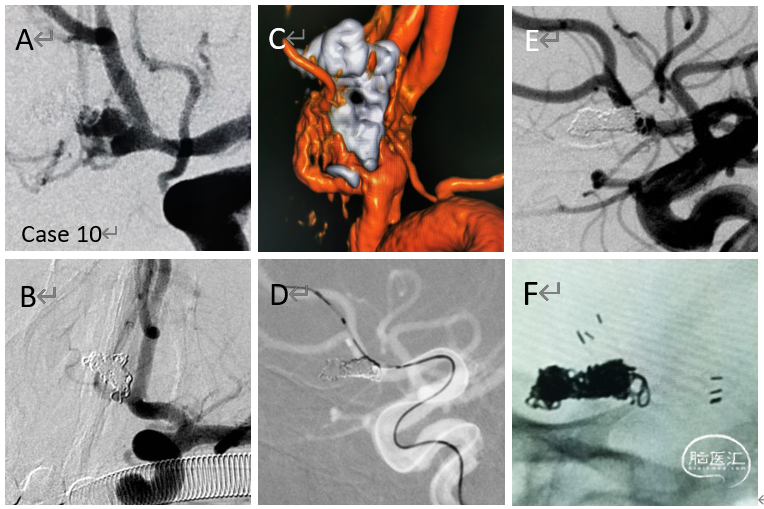

病例10

栓塞的破裂的前交通动脉瘤

(转入)致密栓塞之后二期给予支架植入

病例11

复发的累及PICA的椎动脉夹层动脉瘤

给予追加一枚LVIS,局部推密